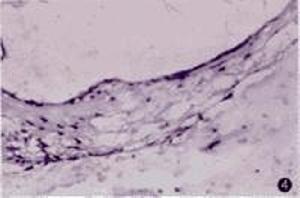

血管紋主要包括邊緣細胞(marginal cell)、中間細胞(intermediate cell)和基底細胞(basal cell)三種細胞成分,具有各自的結構特徵和功能。

中間細胞構成血管紋上皮層主體,細胞間不連續地圍繞在一起,包繞毛細胞血管網,中間細胞是一種從神經嵴遷移分化而來的黑色素細胞,與其他兩種細胞的突起交錯存在。最近有研究者將中間細胞分為基底和頂端兩種亞型,中間細胞的基底亞型形成樹葉狀的水平突起完全覆蓋在基底細胞上,而中間細胞的頂端亞型主要位於血管紋頂端上皮與中間細胞基底亞型之間,並與基底亞型廣泛連線,頂端亞型的樹突狀突起與表層邊緣細胞交錯存在,這種細胞的作用是從基底亞型細胞吸收未進入基底邊緣細胞突起的K+。

來自於發育過程中的間質細胞,形成血管紋的基底部,分隔血管紋與其下方的螺旋韌帶。基底細胞並列相接形成緊密連線的整體,在發育過程中,緊密連線的形成與內淋巴電位的產生是相適應的。